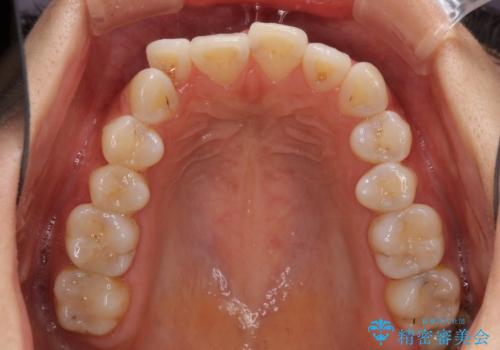

前歯のデコボコが気になる インビザラインによる矯正治療

- 上下前歯のデコボコを気にして来院された患者様です。

インビザラインによる上下歯列の拡大と、IPR(歯と歯の間を削る)にるスペースの獲得により、前歯のデコボコを改善することとしました。

しっかりと装着時間を遵守してくださったので、思い通りの歯列に整えることができました。

結婚式前に終了させることができ、患者様には大変満足していただきました。